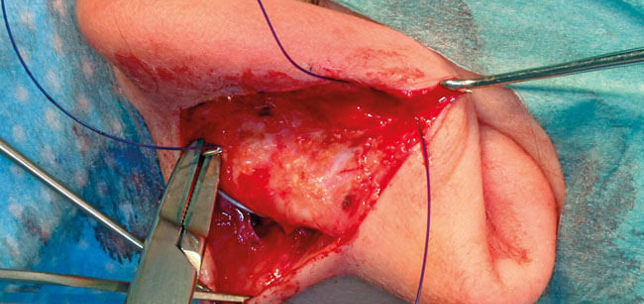

Awake transnasal laryngeal and pharyngeal biopsy in the unsedated patient